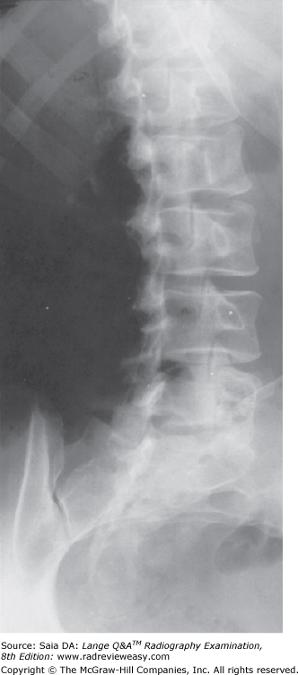

Lumbar Spine Oblique View Radiology Reference Article Radiopaedia Org

X Ray Oblique Views Of The Lumbar Spine Showing The Defect In The Pars Download Scientific Diagram

Oblique View Of Lumbar Spine And Sacrum A Dorsal S1 Foramen B The Download Scientific Diagram

Imaging Techniques For The Diagnosis Of Spondylolisthesis Musculoskeletal Key